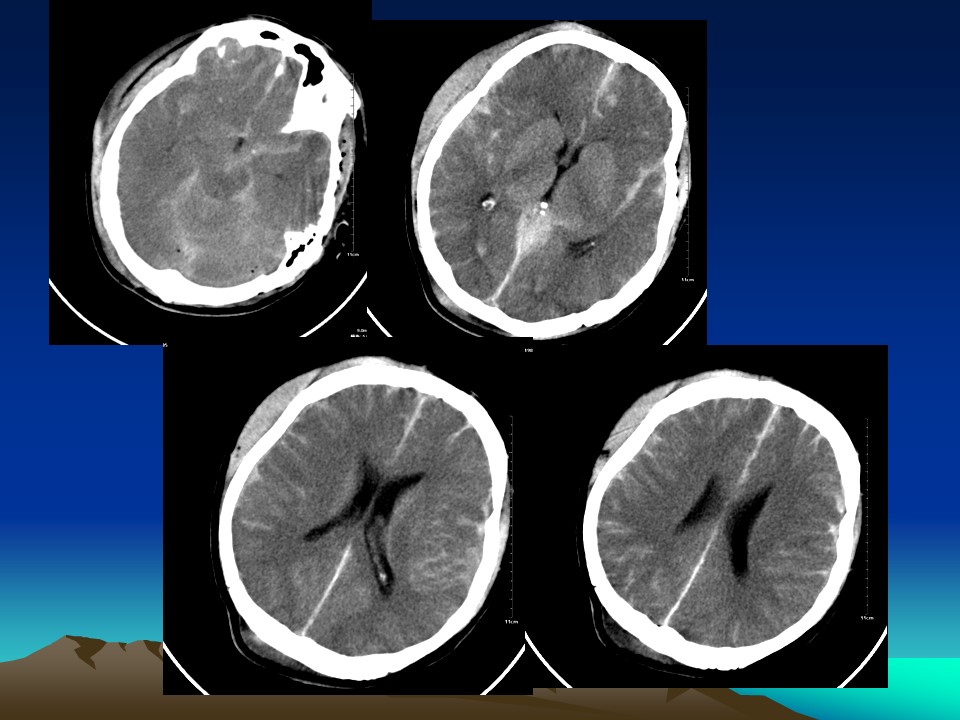

“常见病的CT判读PPT” 的相关文章